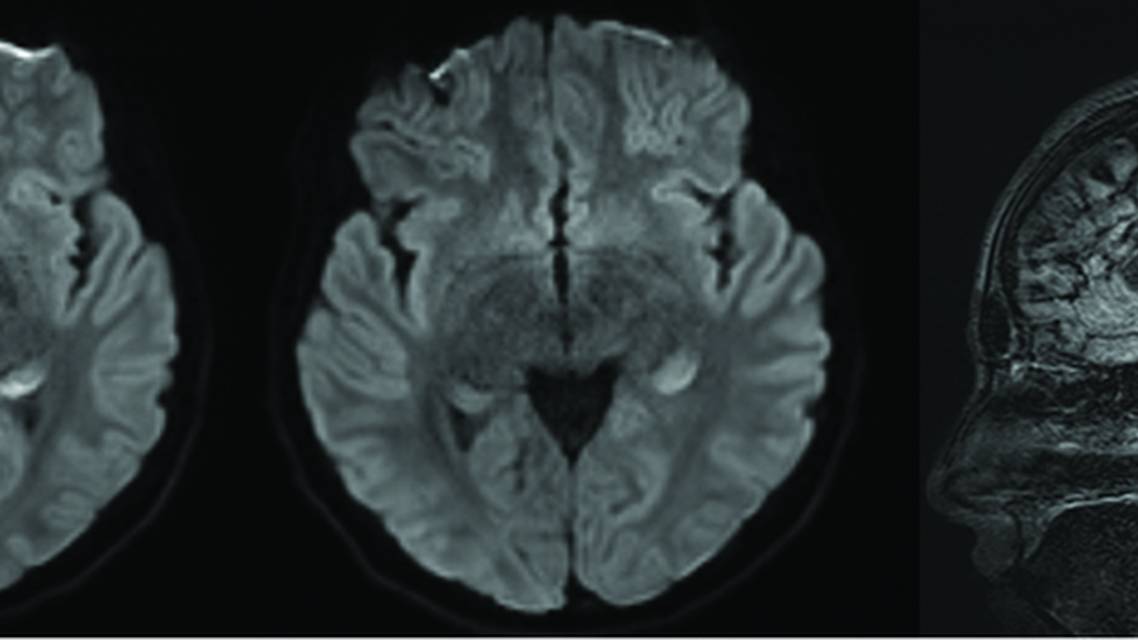

MRI brain scan with and without contrast, although severely limited by motion artifact, revealed a new finding of diffuse cerebellar atrophy compared with a previous study obtained during infancy. A possible poorly visualized region of diffusion restriction and fluid-attenuated inversion recovery abnormality was also evident in the left mesial temporal lobe, which is potentially consistent with postictal changes (Figure 3). These findings, in conjunction with EEG abnormalities, suggest a disturbance in the left cerebral hemisphere in the absence of overt infarction.

Figure 3. Two axial slices and 1 sagittal slice from brain MRI fluid-attenuated inversion recovery imaging. The axial images show left medial temporal hyperintensity, believed to be secondary to seizure-related edema and high levels of expression of the CACNA1A calcium channels in the region. The sagittal image displays the substantial cerebellar atrophy that can be associated with this condition.

Imaging results also demonstrated marked cerebellar atrophy, which is a recognized feature of CACNA1A-related disorders.13 Although the timing and progression of this abnormality are uncertain because UL last underwent brain imaging in infancy, the need for structured evaluation throughout development is clear. We also noted asymmetric fluid-attenuated inversion recovery signal in the left mesial temporal lobe, which was believed to be most consistent with postictal edema given the known overlap between CACNA1A channelopathies and seizure susceptibility.